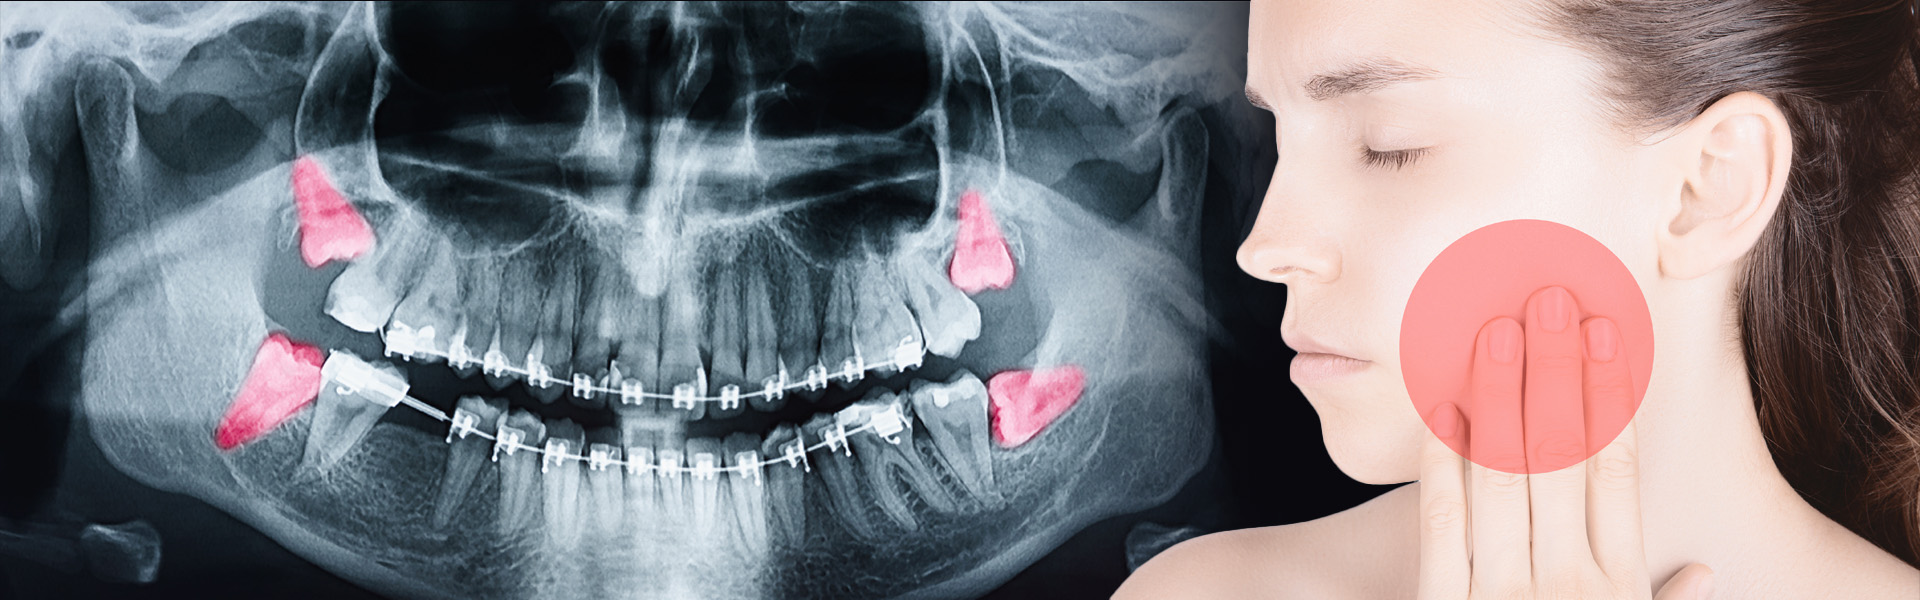

Most people’s mouths only have enough room for 28 teeth. When your wisdom teeth start to come in, that’s four additional teeth trying to make their way in.

In most situations, this creates a litany of problems, including crowding, soreness, risk of decay in adjacent teeth, risk of infection and the need for extraction.

With radiographs and a thorough examination, we can determine if your wisdom teeth are impacted and need to be removed. Since wisdom teeth rarely come in straight and even with the rest of your smile, we have years of experience analysing and extracting them at The Ackerman Clinic.